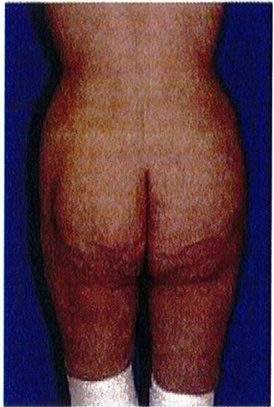

Bước cuối cùng khi đánh giá vùng mông là đánh giá tình trạng sa mông. Đế đánh giá, nên đứng ỏ phía bên để nhìn và phân loại sa mông (từ không sa đến có sa), cả 2 loại này đều được phân loại thành 3 phân lớp phía dưới chúng. Việc phân loại này quyết định xem nên thực hiện quy trình nào cho bệnh nhân.

Ở những bệnh nhân không có sa mông, toàn bộ vùng mông nằm trên nếp lắn mông và không có phần da thừa nằm dưới nếp lằn.

Tuy nhiên, dựa trên hình dạng vùng mông của đa số những bệnh nhân này, có thể chia thành 3 lớp: A, B và C (Hình 27).

Phân loại sa mông

Phân loại này được áp dụng khi có vùng da sa xuống dưới nếp lắn mông và chúng được chia thành 3 giai đoạn I, II, III (Hình 28).